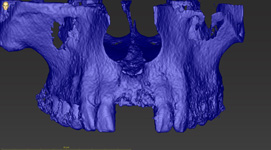

Lékař si vytvoří všechny typy zobrazení potřebných pro naplánování – tedy 2D snímky (panoramatický), příčné řezy i 3D model.

Vidí zde i důležité anatomické útvary – čelistní dutinu, průběh nervu atd. Po proměření množství kosti – šířky i výšky vybere z databáze vhodný typ implantátu a umístí ho do požadované lokality. Ihned vidí jeho pozici ve všech 3 rovinách a na všech snímcích i 3D modelu. Může upravovat podle potřeby jeho pozici, sklon atd.

Všechny vybrané a správně umístěné simulované implantáty se ukládají do „počítačové karty“ pacienta s jejich pozicí, délkou, průměrem, typem i sklonem. V programu také lékař navrhuje chirurgické šablony pro řízenou nebo navigovanou implantaci. Lékař i pacient tedy ještě před vlastní operací vidí, jak by mělo ošetření probíhat a vypadat.